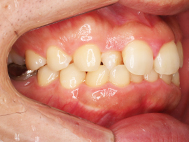

After

| 症状 | 上顎前歯部叢生 |

上の前歯がハの字隣の歯が引っ込んでいる

前歯のガタガタが気になるとの事で来院されました。

装着が目立ちたくないとの事でアライナ-での矯正を希望されました、歯の間を削り少し歯の幅をスリムにして綺麗なアーチに並びました。